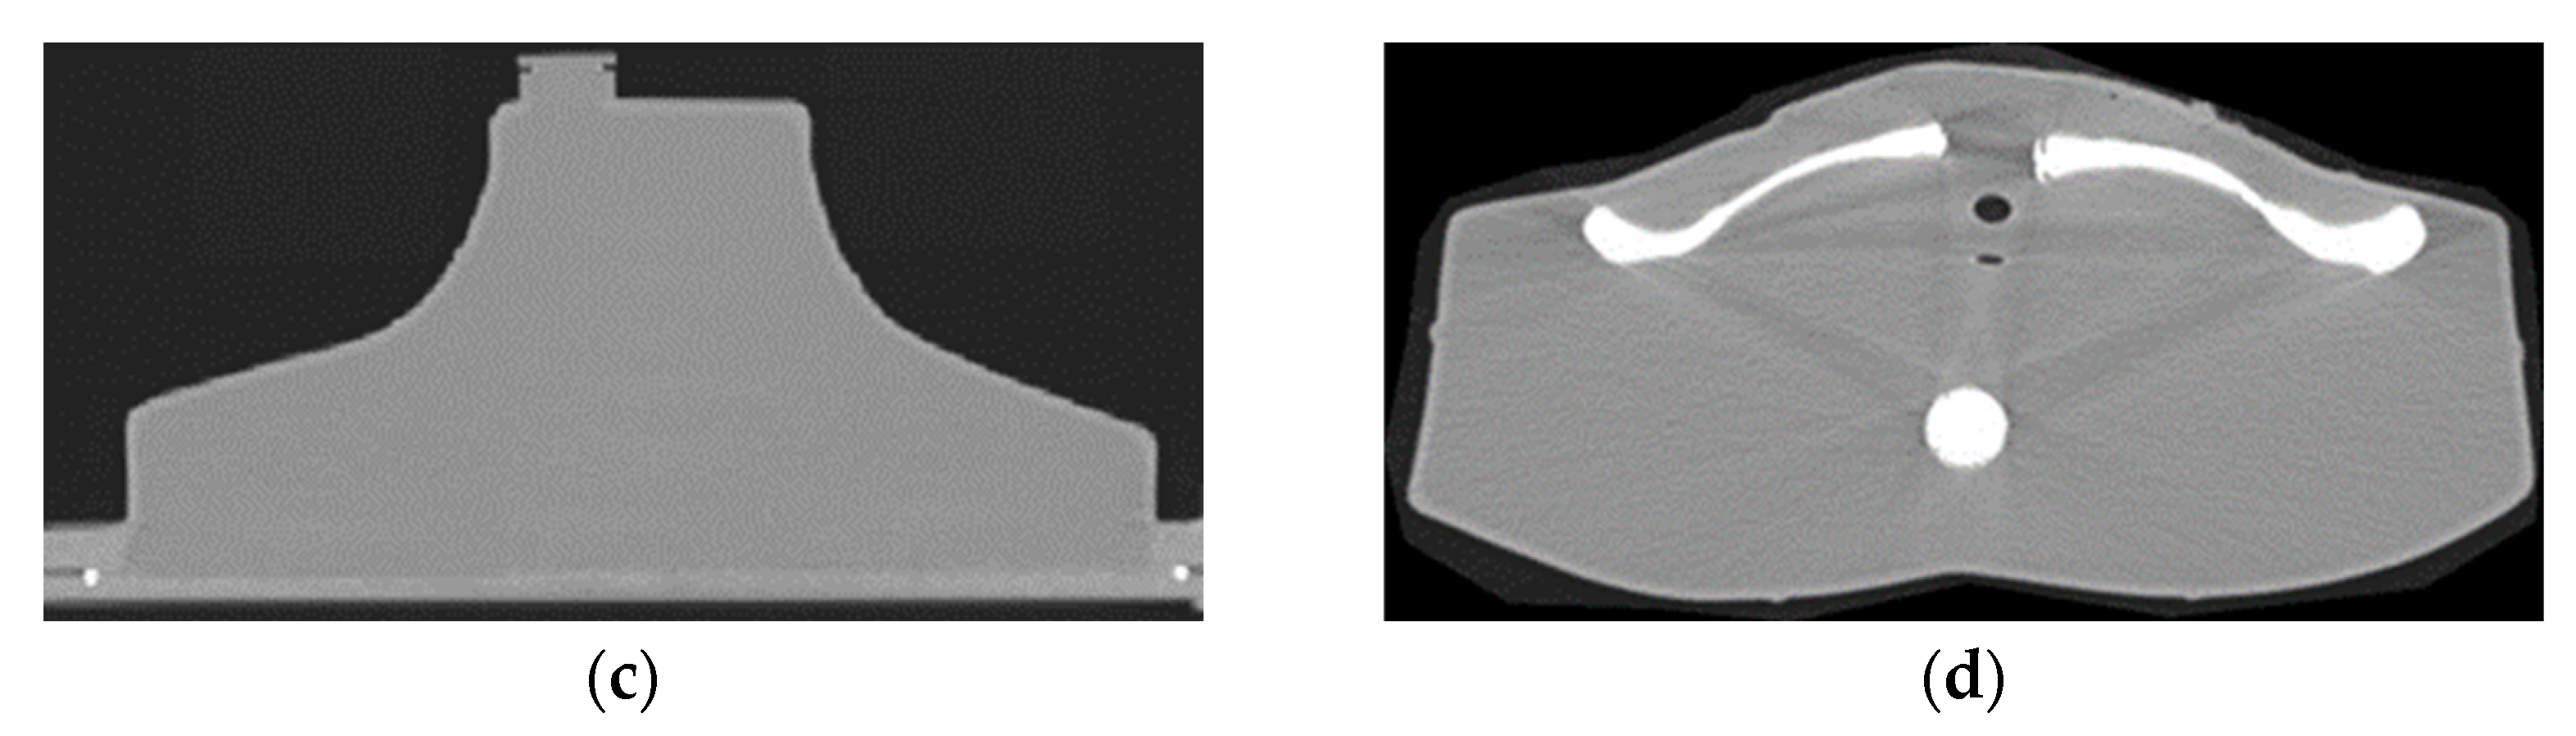

Figure 10 shows an axial CT slice through the center of the 1.5- and 3-mL thyroid remnants, a sagittal CT slice through the center of the spine, a coronal slice through the center of the phantom (between the esophagus and cervical spine) and an axial CT slice through the bottom part of the phantom showing a top view of the clavicle. It should be noted that the hollow cavities of the neck phantom and the remnants were filled with water. It can be observed that the structures within the phantom were anatomically positioned according to a sectional anatomy atlas [30], and their densities were uniform. In addition, the X-ray contrast between the various structures was satisfactory according to the sectional anatomy atlas [30] for distinguishing the structures. Only minor streaking artifacts can be observed close to the bones.

Figure 10. (a) Axial CT slice through the center of the 1.5- and 3-mL thyroid remnants; (b) sagittal CT slice through the center of the spine; (c) coronal slice through the center of the phantom (between esophagus and cervical spine); and (d) axial CT slice through the bottom part of the phantom showing a top view of the clavicle. The phantom was filled with water.